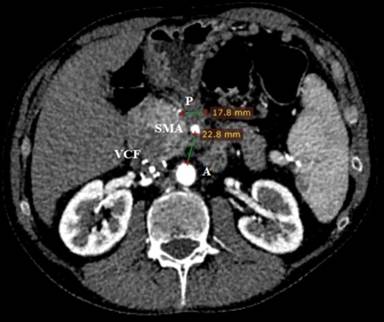

Twelve months after the HIFU ablation, CT revealed a decreased tumor size to 18 mm (Figure 6). An objective anatomical landmark, confirming the shrinkage of the formation during the patient follow-up was the distance between the aorta and the superior mesenteric artery. Before HIFU ablation the distance was 8.2 mm, and 12 months later it reached 23 mm (Figures 3 and 6). The control CT also showed remarkable reduction of the liver metastases (Figure 2c). The quality of life evaluated by the same EORTC instruments remained stable.

Figure 6. Control contrast enhanced CT (12 months after HIFU). There is significant reduction of the ablated tumor (P) to 18 mm. The distance between the aorta (A) and the superior mesenteric artery (SMA) was 23 mm. |